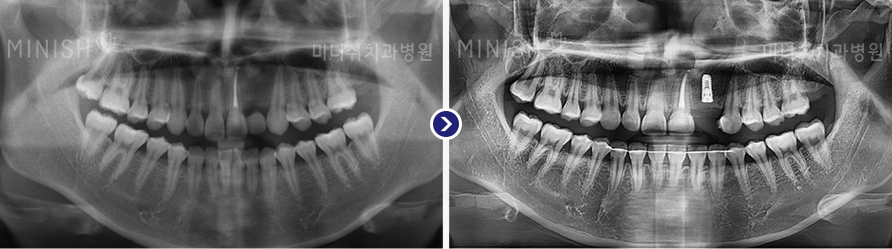

种植牙前后变化

01 X光片